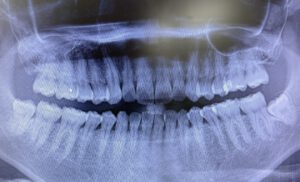

当院では最新のレントゲン撮影装置やCTの設備を使用して、親知らずの状態や位置を詳しく調べます。事前に検査を実施することにより、治療の精度を向上させ患者様にとってのリスクを軽減することができます。

レントゲン検査では、親知らずの位置や形・歯根の形などを確認します。レントゲン撮影後、必要な場合はCT撮影を行うこともあります。